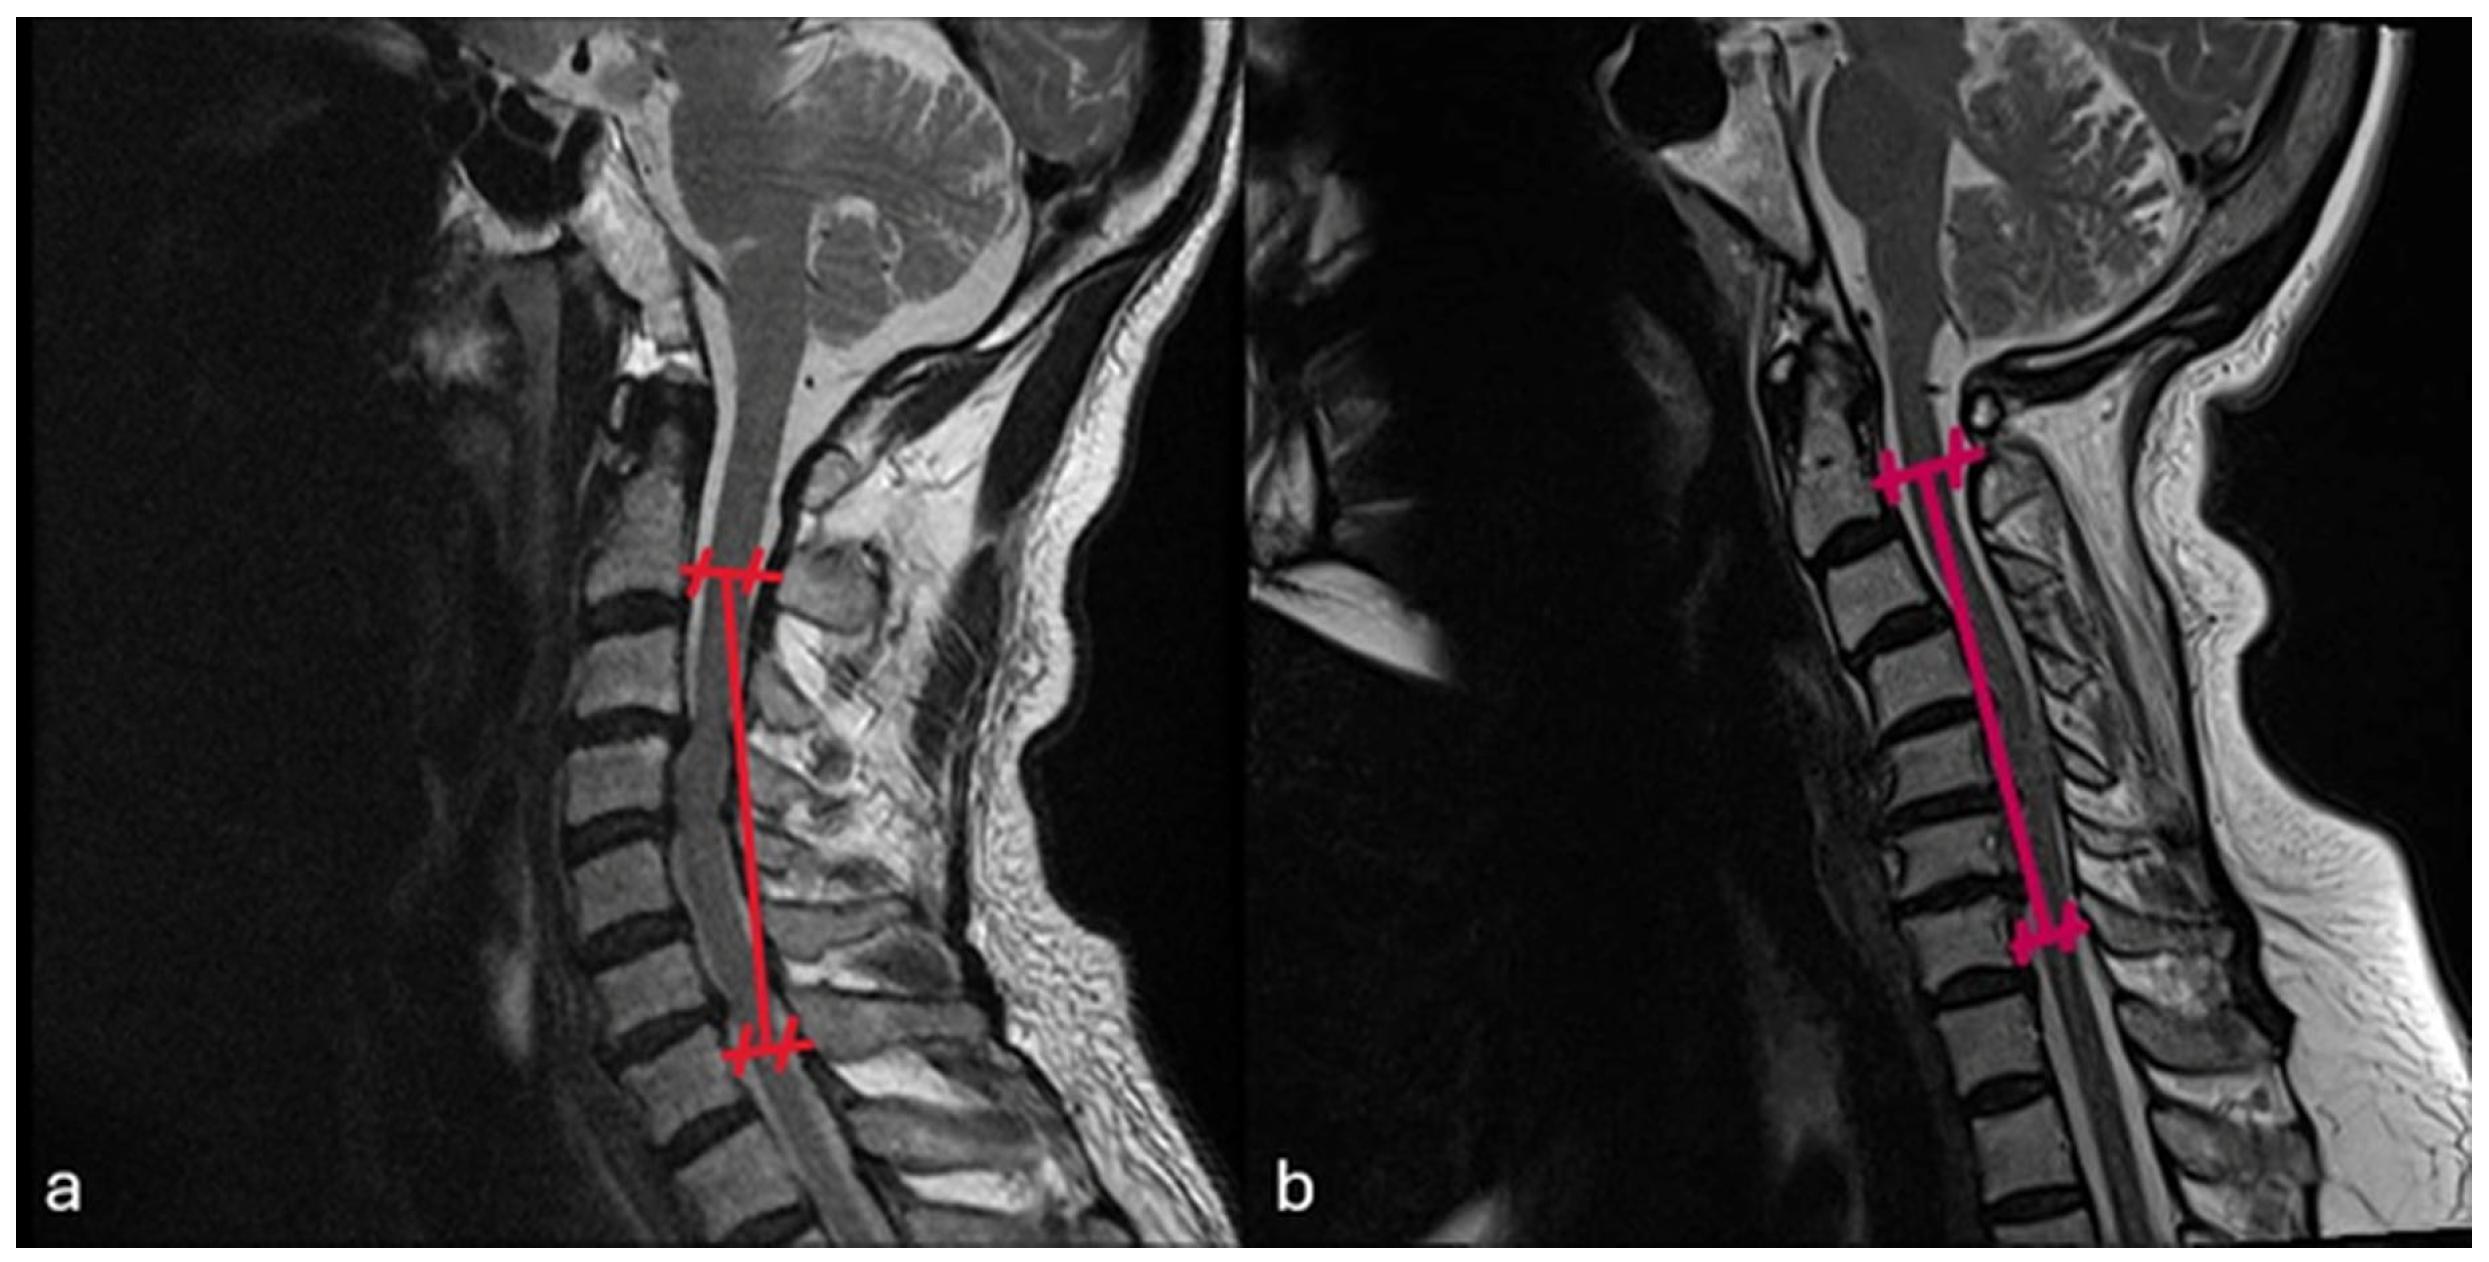

Preoperative C2–C7 Cobb Angle vs. Postoperative Last Control C2–C7 Cobb Angle

Preoperative Cervical Alignment Category vs. Postoperative Cervical Alignment Category

Preoperative K-Line vs. Postoperative K-Line